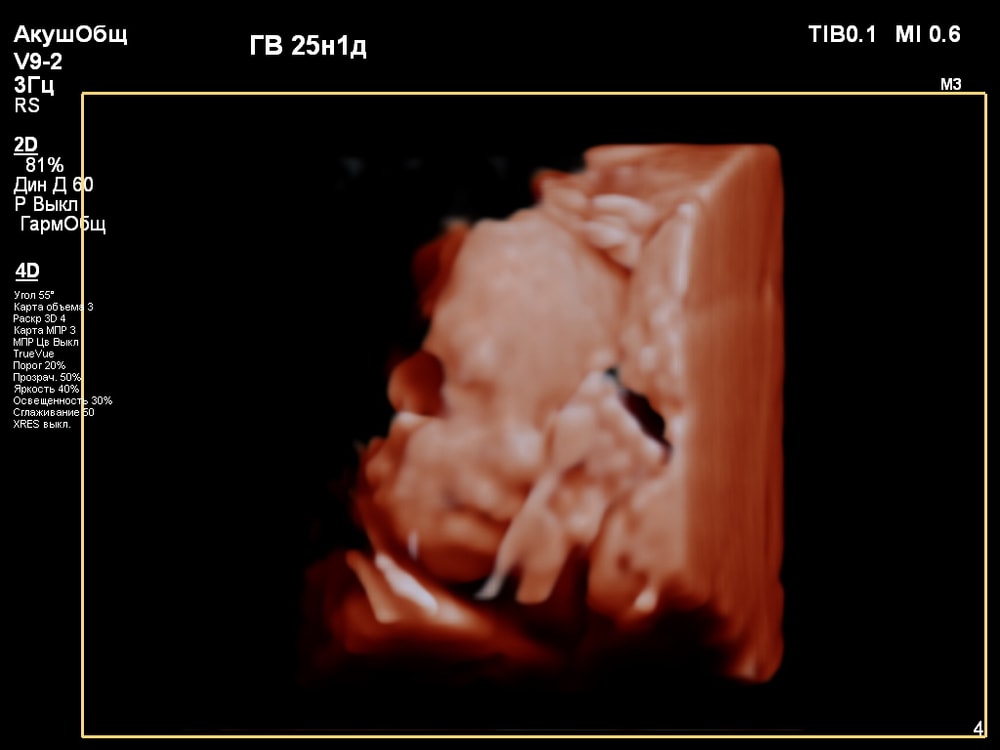

3D/4D УЗИ в 25 недель

УЗИ, КТГ, доплерПервая фотосессия малыша ещё в животике!😍 СНИМКИ С УЗИ👇

Когда переключили на 4D режим было сначала непонятно, что изображено на экране. Но врач всё показывала и обьясняла что на нём: где носик, губки, подбородок, что у личика ручки, малыш что-то жуёт, губками шевелит. Тогда картина начала вырисовываться и всё стало понятно, и в движении тоже)).

За 30 мин удалось увидеть многое (ребёночек не спал)! Он у меня в принципе парень активный, особенно лёжа на спине): на УЗИ, ещё в самом начале, малыш показал указательный палец и почесал им нос 😂, потом пытался большой палец засунуть в рот и пососать. Забавно было, когда он начал зевать и прикрывать ротик ладонью (воспитанный растёт). Ну и конечно, на радость родителям малыш улыбался🥰. Александра Евгеньевна смогла поймать все эти моменты и запечатлеть на снимке). Когда ребёночек закрывался, отворачивался - врач проводила общее 2D исследование, потом возвращалась к 4D.

Иногда получить хорошую картинку сложно. Качество изображения сильно зависит от положения плода, количества околоплодных вод, расположения плаценты, толщины брюшной стенки. Мне в этом плане повезло, плацента была расположена по задней стенке матки, брюшная стенка у меня тоненькая, околоплодные воды в норме, малыш был в движении и можно было разглядеть его профиль.